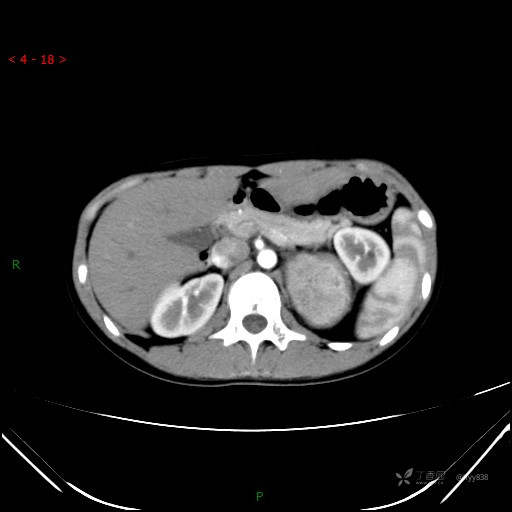

腹部CT平扫